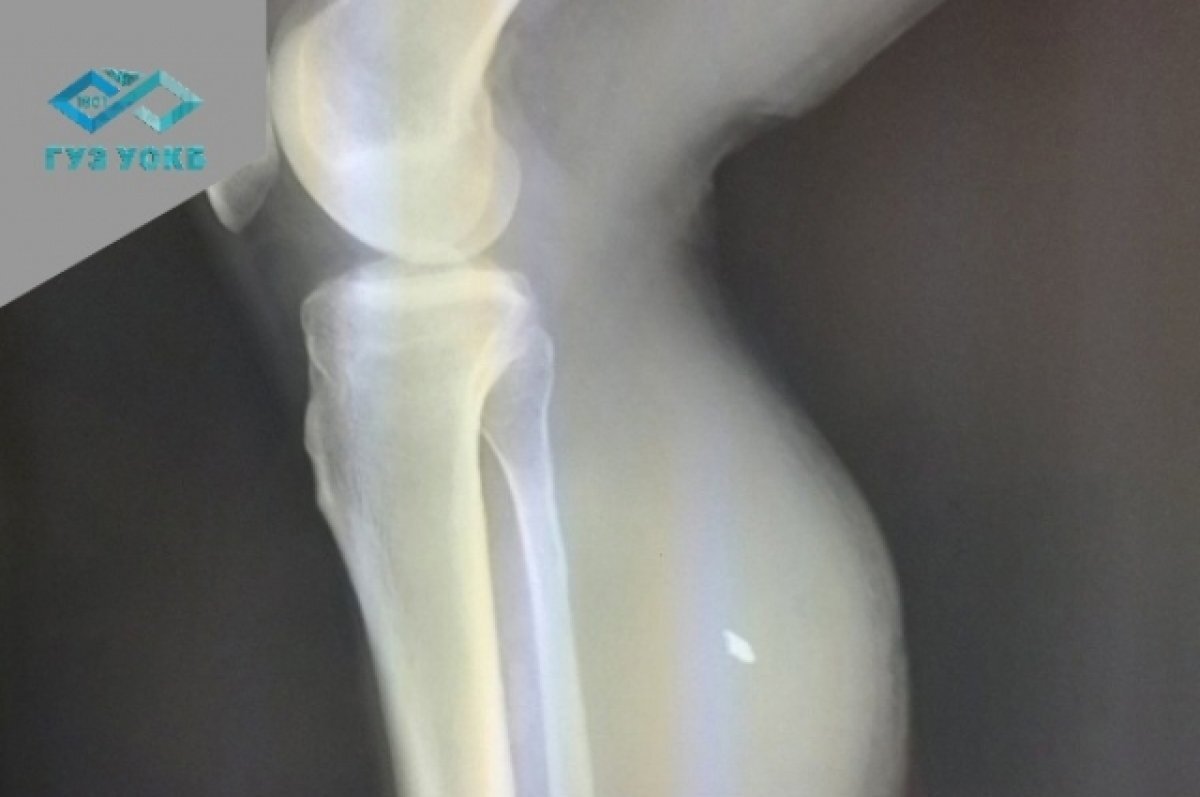

Как рассказал и.о. заведующего торакальным сосудистым отделением больницы Сергей Мустафин, в правой голени мужчины был обнаружен пятимиллиметровый осколок, который повредил малую берцовую артерию – в результате образовалась посттравматическая ложная аневризма объёмом 500 мм.